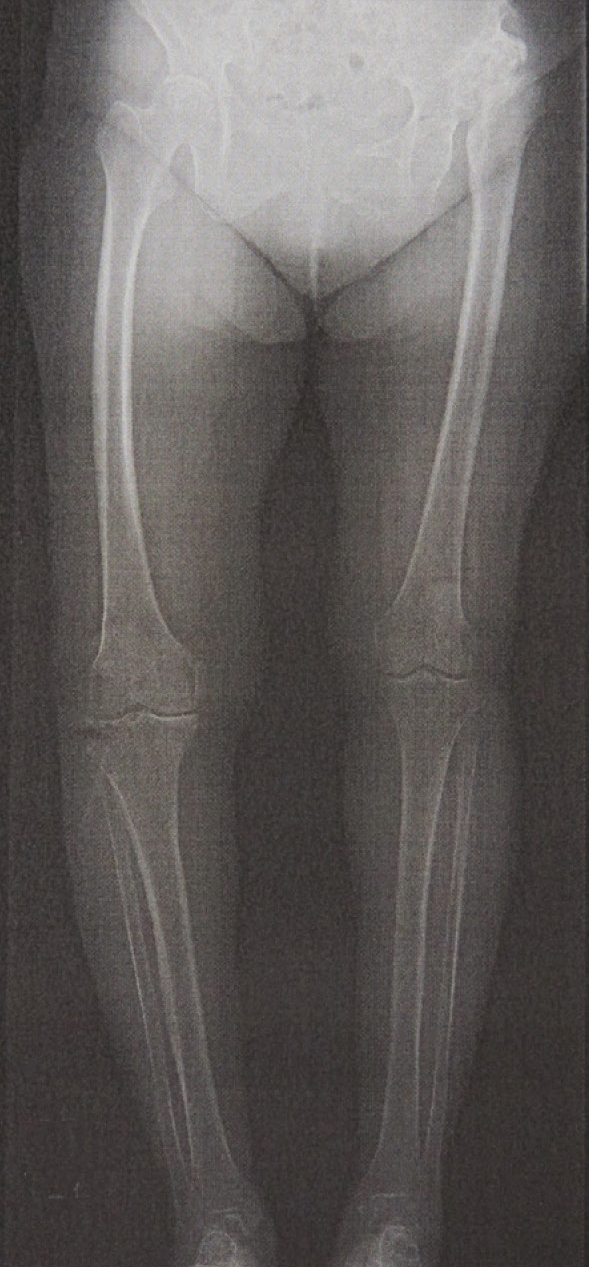

下肢全体を含めたアライメント(骨の並び)をレントゲンで確認します。

そのため、まず脊椎や下肢全体を含めたアライメント(配列)をレントゲンで確認し、他の可能性を見落とすことのないよう、脊椎も含めた専門医同士で連携を進めています。

変形性膝関節症のレントゲン